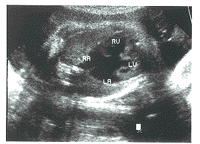

先心病组TR均有心内结构异常。其中:肺动脉狭窄3例,表现肺动脉瓣环或内径缩小,右房显著扩大,右室壁肥厚(图1)。左心发育不良综合征2例,表现左心房、室缩小,主动脉缩小,右心房、室及三尖瓣环扩大(图2)。完全型心内膜垫缺损1例,表现房间隔及室间隔上部缺失,心腔相互交通,房室瓣发育异常,形成左右心室共同房室瓣(图3)。

四腔观:十字交叉点消失,各心腔相互交通,房室瓣发育异常

图3 心内膜垫缺损